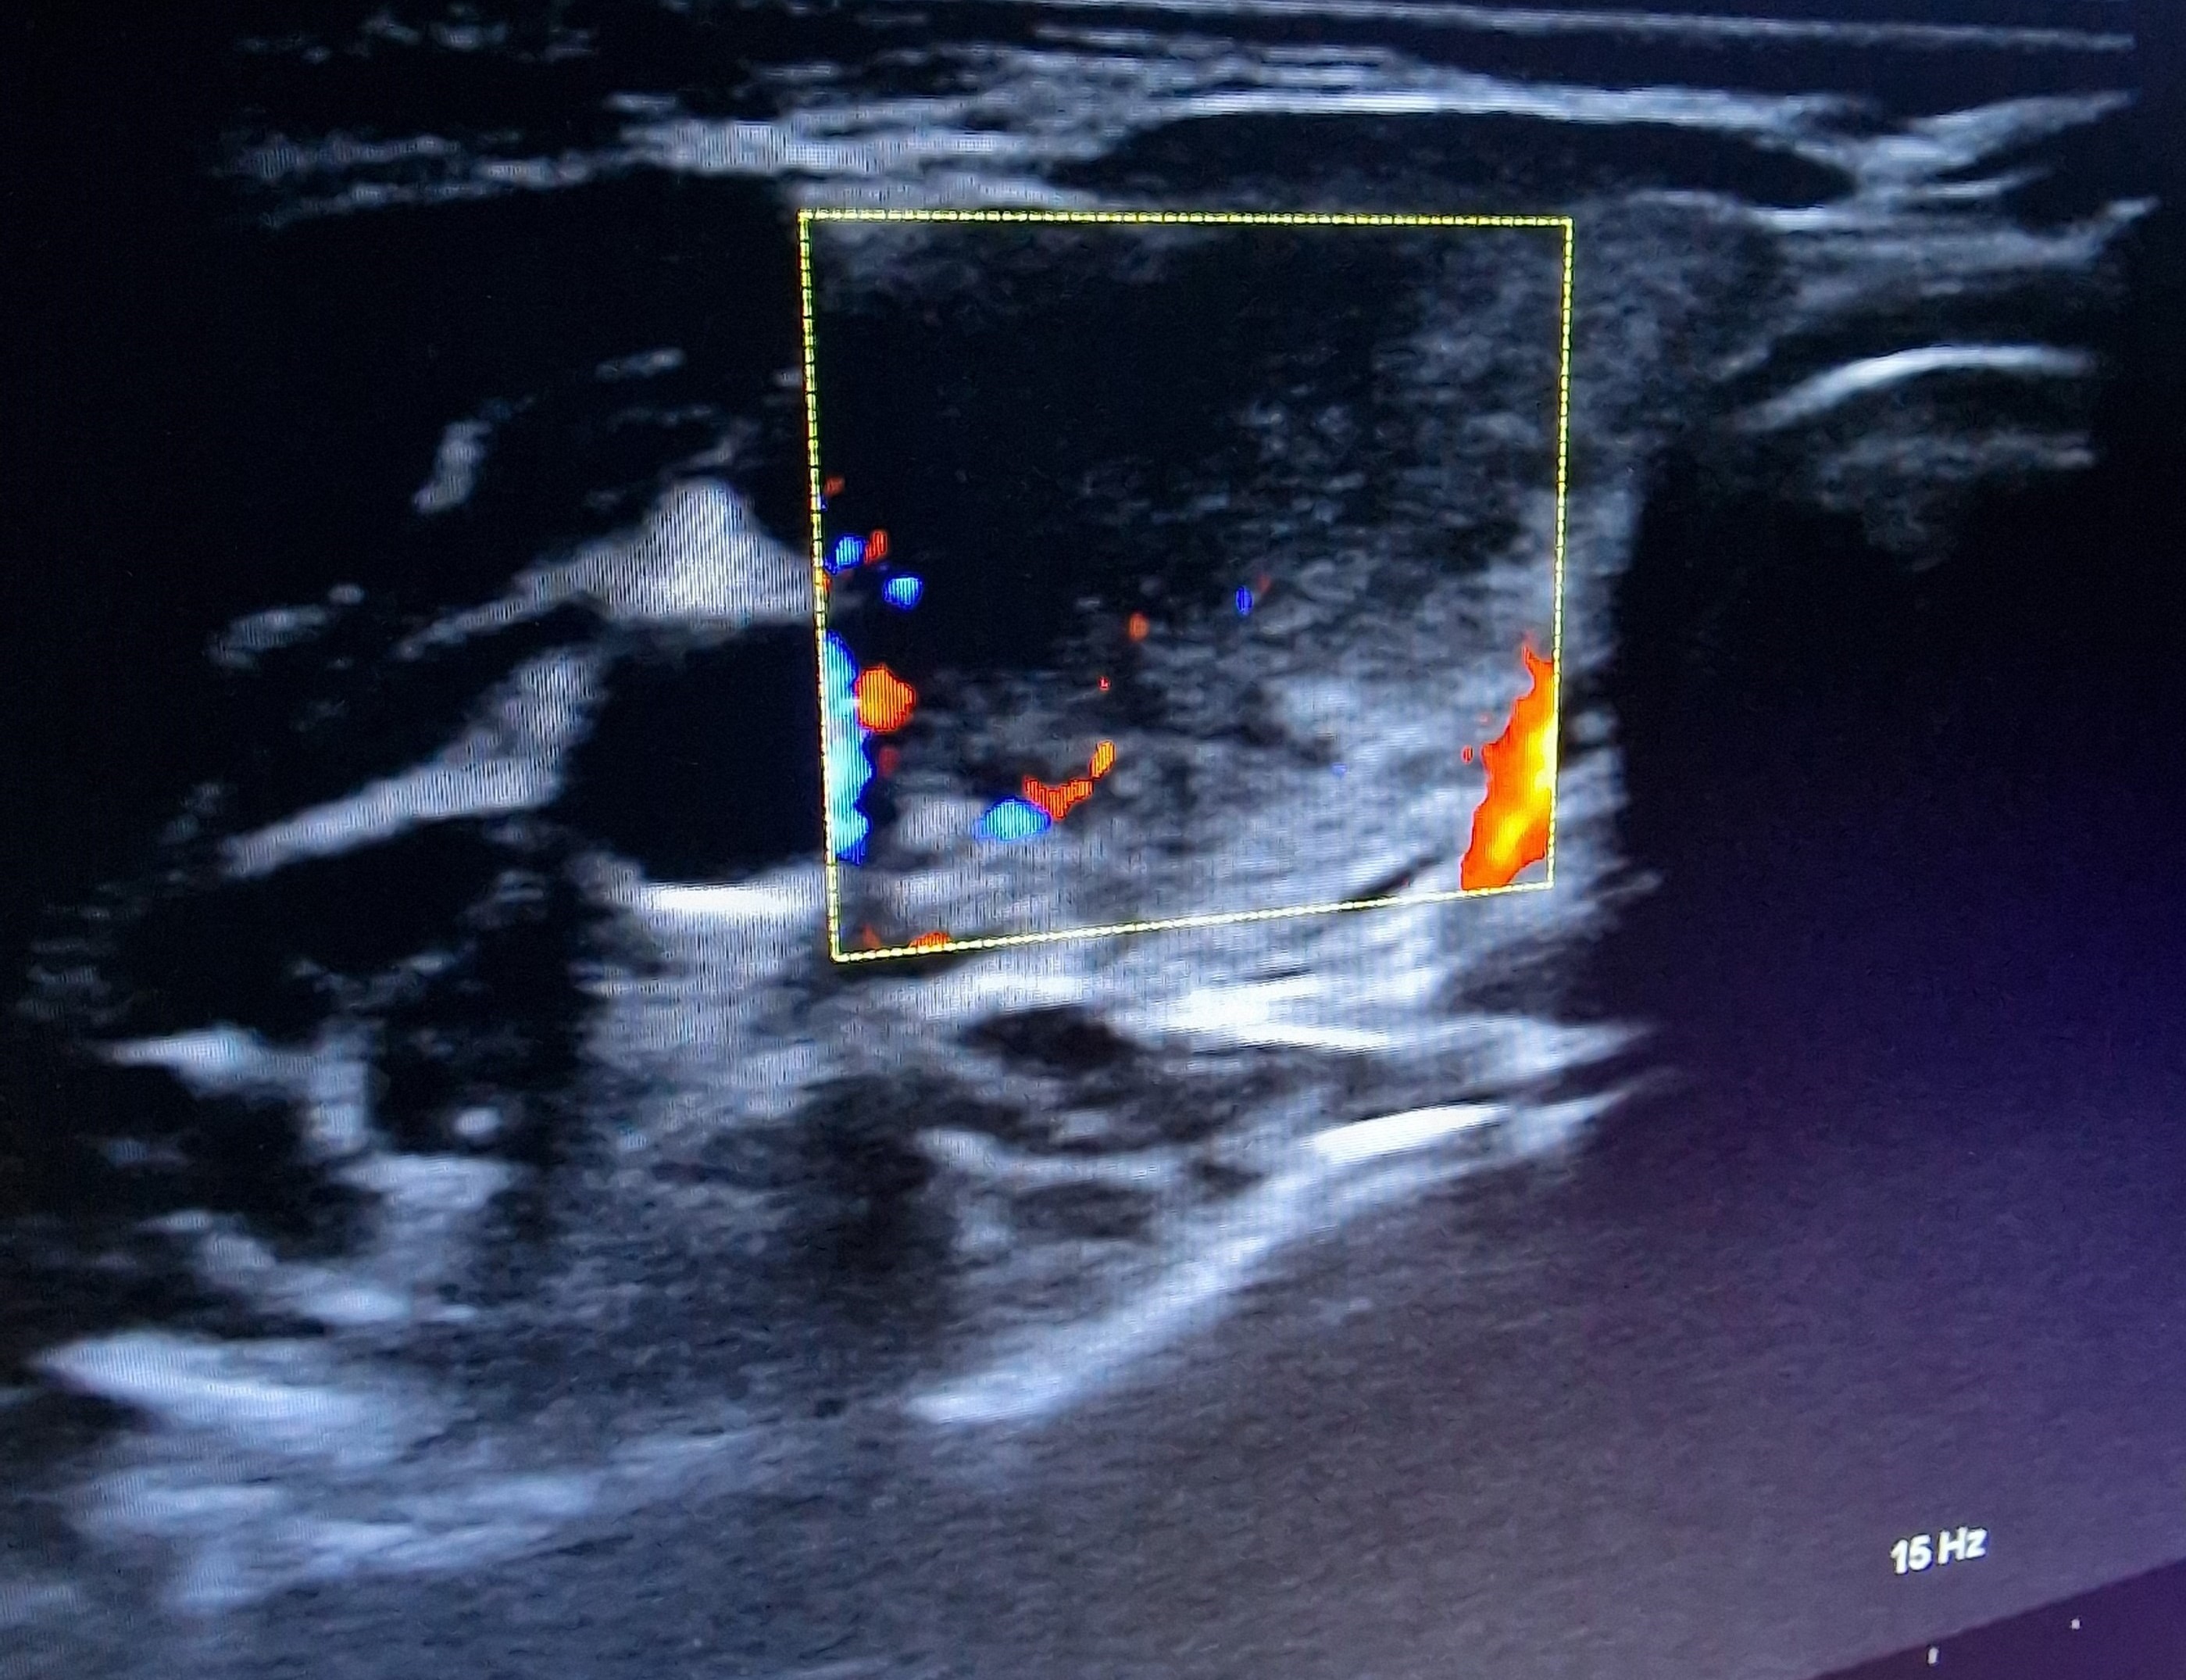

Ecografía cervical: tiroides de ecogenicidad heterogénea con áreas hipoecogénicas y ausencia de vascularización de éstas, Lóbulo Tiroideo Derecho 20 x 14 mm con nódulo < 10 mm no maligno e izquierdo 16 x 12 mm.

El diagnóstico diferencial se realizará con procesos infecciosos de vías respiratorias altas, con tiroidopatías con hipertiroidismo y ecogenicidad disminuida (enfermedad de Graves, patrón hipervascular; tiroiditis supurativa aguda), carcinoma tiroideo, hemorragia de nódulo tiroideo.